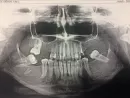

С конца декабря стала побаливать челюсть слева не сильно. Я обратилась к стоматологу сделали снимок, зуб крайний слева сверху лечила 2 года назад. Была пломба, которая вылетела год назад, зуб больше не лечила. У зуба нижнего крайнего слева кариес, врач сказал, что никакого процесса нет, что надо делать имплантацию зуба, отложила этот вопрос до лета, отпуска, с зубами у меня конечно проблема, я не спорю.

7 февраля у меня воспалился подчелюстной лимфоузел. Обращалась к ЛОР врачу, стоматологу, они сказали, что это не из-за зубов, терапевт прописал антибиотики. Я пропила 5 днейЮ мне помогло, но через 10 дней воспалились уже лимфоузлы на шее, опять пошла по всем врачам. Пошла к стоматологу, сделали повторный рентген, ничего не нашли. Обратилась к инфекционисту, который опять прописал антибиотики из тоже класса, что и в первый раз, но посильнее и на 7 дней. Пропила стало сразу же лучше, но прошло ещё 5 дней, и у меня воспаляются затылочные лимфоузлы, опять по врачам, сдавала анализы, кровь хорошая, на ВИЧ, гепатит сдала, тоже все в норме, была у гематолога-онколога, тоже все в норме, делала УЗИ лимфоузлов, тоже патологий нет. Положили в "инфекцию" все-таки потому, что была маленькая температура, и ходила я опять к своим любимым стоматологам.

Уже 3- й стоматолог сказал, что не в зубах причина. Смотрели меня очень хорошо, претензий нет, просто причину не нашли, а как-то все равно побаливает челюсть, я все ещё лежу в госпитале, а причину не найдут. 2 снимка, первый декабрь 2016, второй февраль 2017.

В снимках отличий практически нет.

Два момента - при длительном отсутствии жевательной группы зубов увеличивается нагрузка на височно-нижнечелюстной сустав, в нем могут произойти изменения и как следствие - воздействие на одну из ветвей тройничного нерва.

Что касается лимфоузлов, стоит посмотреть внимательнее слюнные железы на предмет застойных явлений и наличия камней в протоках. Кроме этих двух мыслей ничего сказать не могу — по снимкам в зубах проблем не наблюдается, только отсутствие большого количества и корень справа снизу.